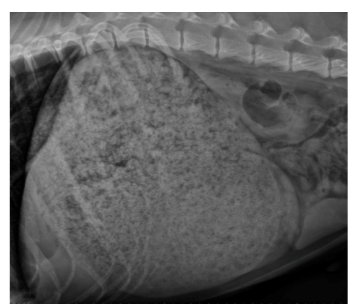

survey radiographs

contrast radiography

fluoroscopy

Thoracic radiographs - best single test for esophageal disorders

Thoracic rads*

contrast esophagram* or CT angiography